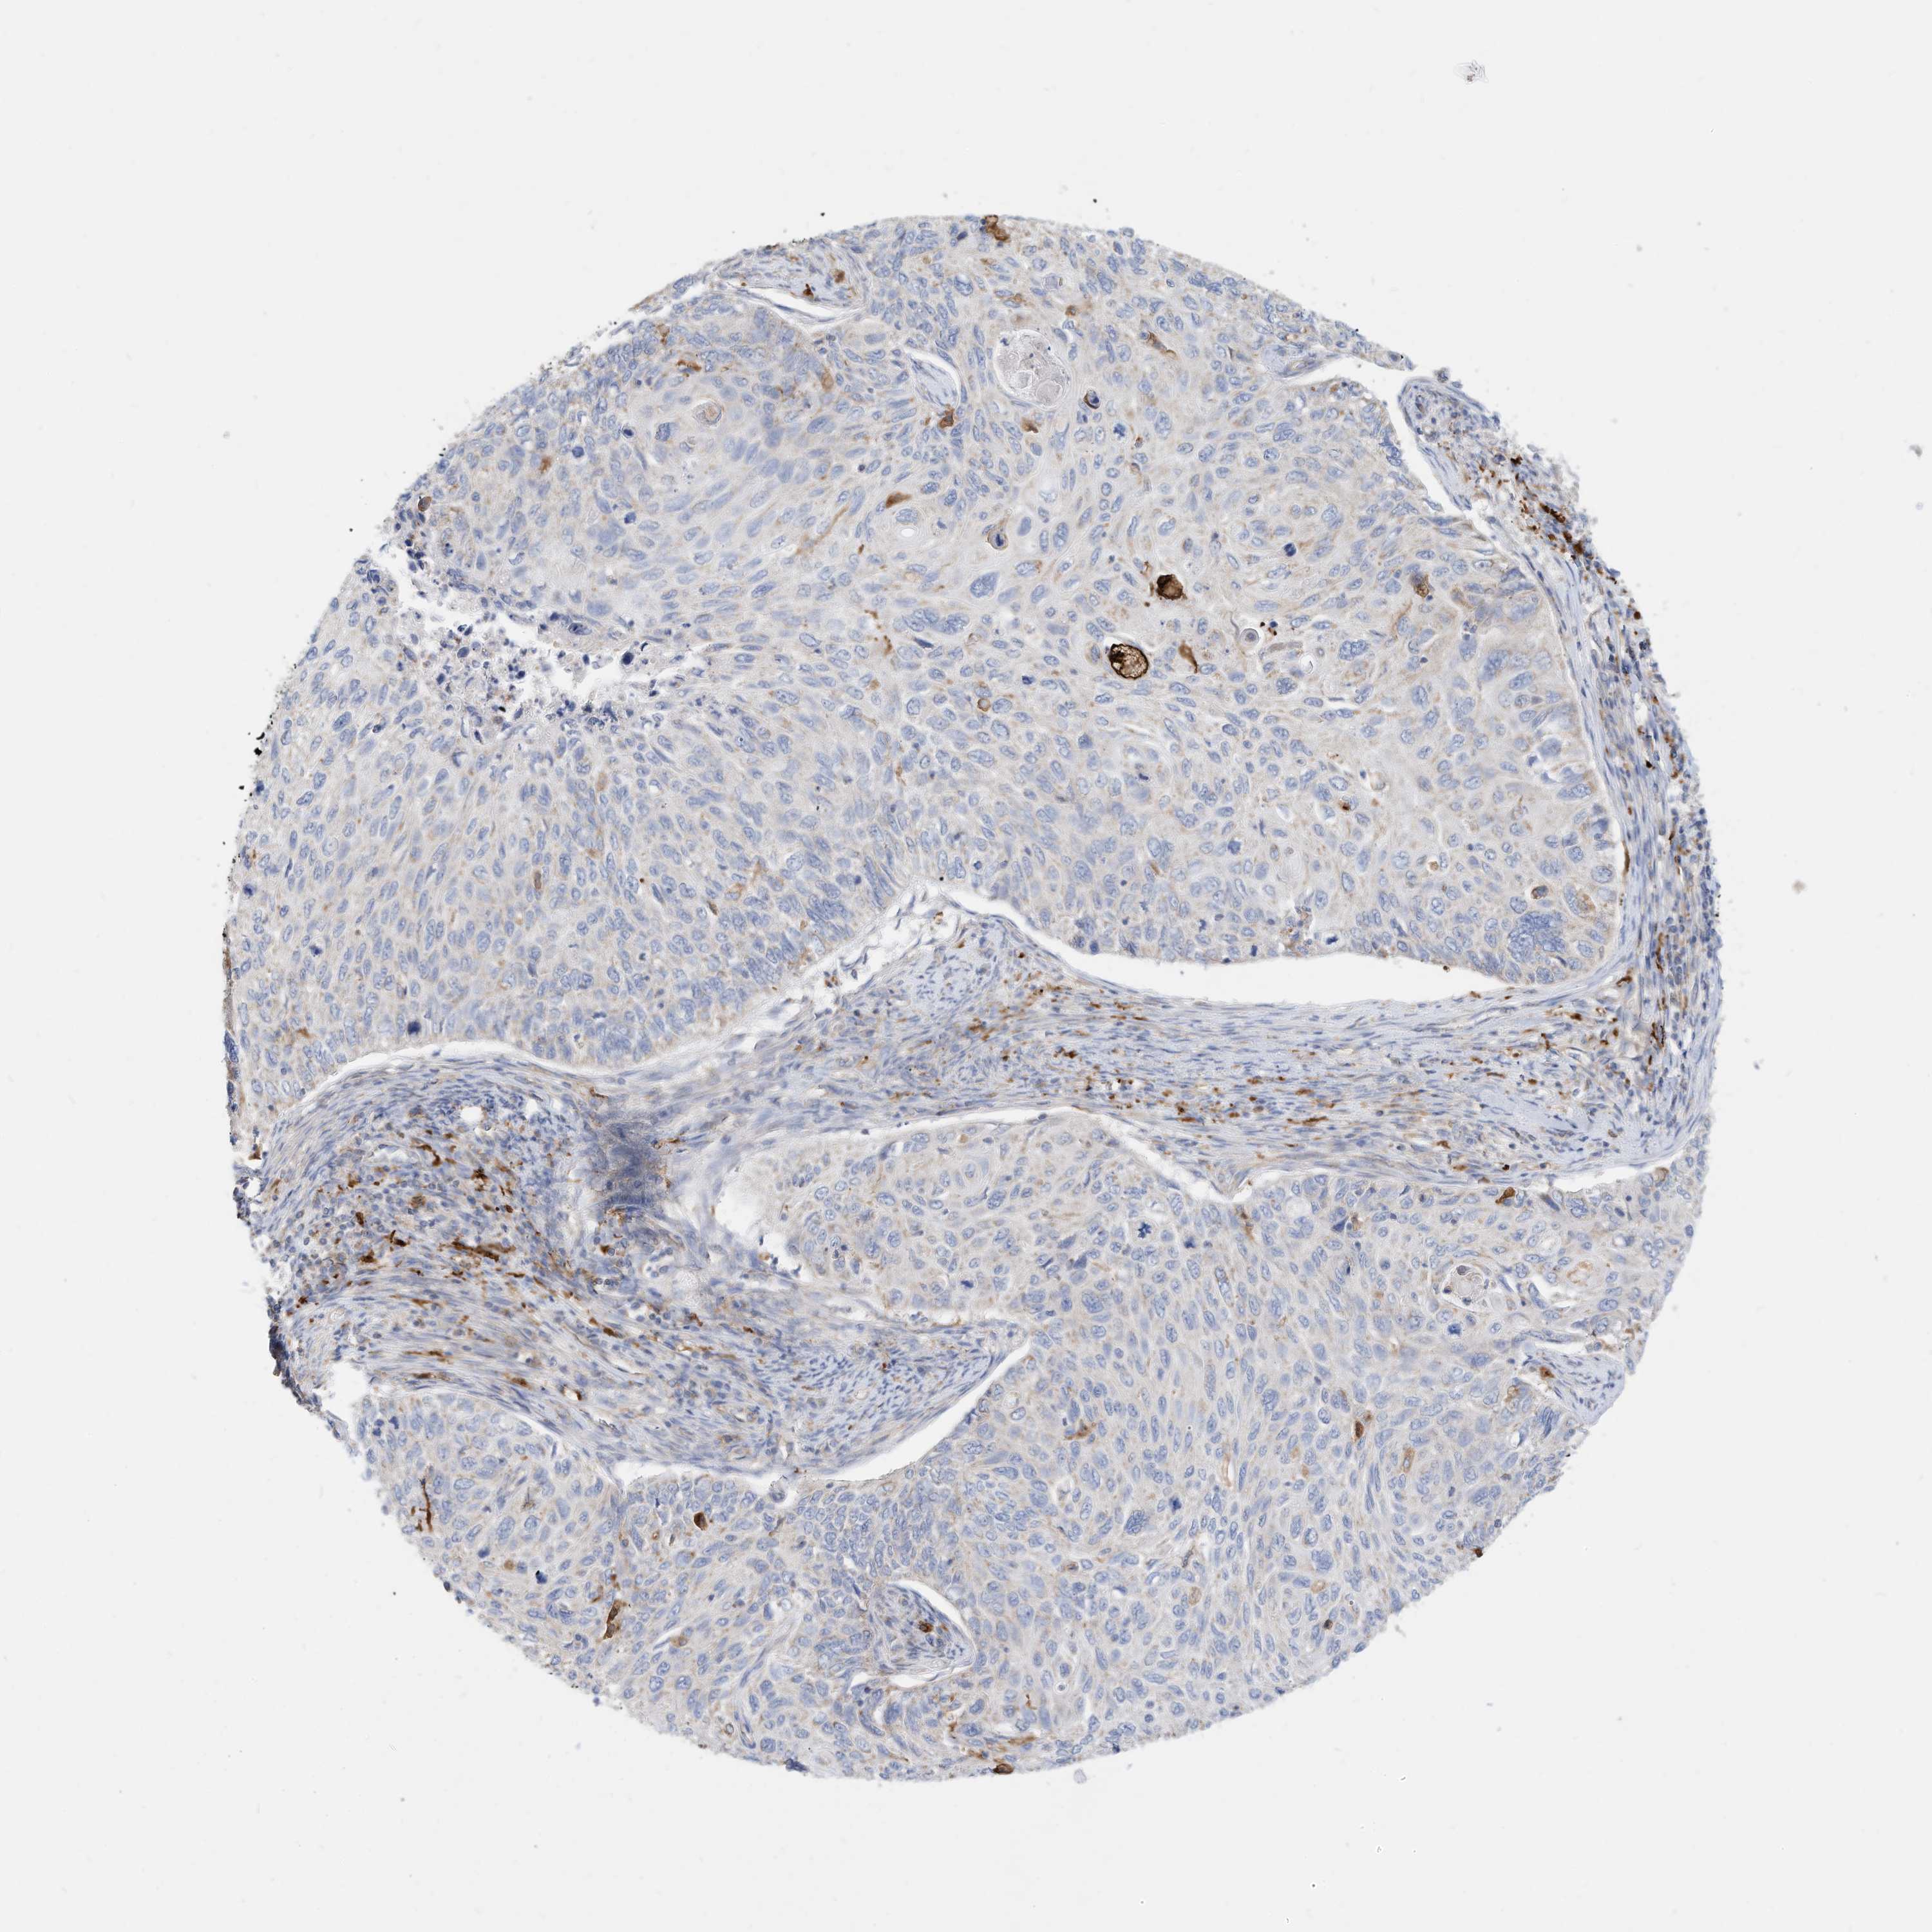

CERVICAL CANCER - Protein expressioni

A mouse-over function shows sample information and annotation data. Click on an image to view it in a full screen mode. Samples can be filtered based on level of antibody staining by selecting one or several of the following categories: high, medium, low and not detected. The assay and annotation is described here.

Note that samples used for immunohistochemistry by the Human Protein Atlas do not correspond to samples in the TCGA dataset.

Antibody stainingi

Antibody staining in the annotated cell types in the current human tissue is reported as not detected, low, medium, or high, based on conventional immunohistochemistry profiling in selected tissues. This score is based on the combination of the staining intensity and fraction of stained cells.

Each image is clickable and will lead to virtual microscopy that enables deeper exploration of all samples and also displays staining intensity scores, fraction scores and subcellular localization as well as patient and tissue information for each sample.

Antibody HPA030345

Staining

High

Medium

Low

Not detected

Intensity

Strong

Moderate

Weak

Negative

Quantity

>75%

75%-25%

<25%

None

Location

Nuclear

Cytoplasmic/membranous

Cytoplasmic/membranous,nuclear

Squamous cell carcinoma, NOS

Adenocarcinoma, NOS